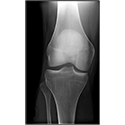

LOWER LIMB

Interactive Radiology